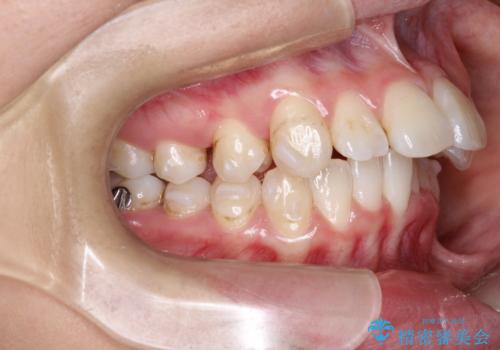

- 初診時には上顎前歯の突出、前歯部の深いかみ合わせ、叢生が見られる状態でした。

このケースでは非抜歯にて奥歯を後方に移動させる事で前歯の突出を改善するスペースを作り出していますが、これはマウスピースと顎間ゴムの併用によるもので、患者様のご協力の賜物と言えます。

使用した装置はマウスピースと顎間ゴムのみです。ワイヤーやマイクロインプラントなど補助装置の使用はありません。